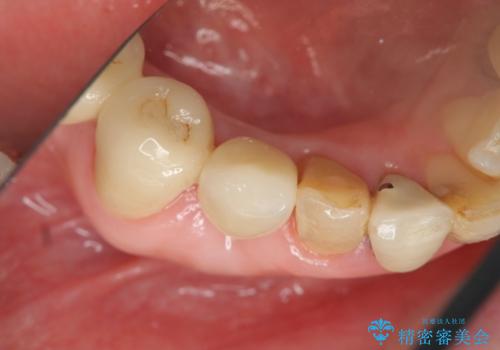

吸収した骨の再生 前歯部インプラント治療

抜歯後、インプラントによる審美・機能改善を希望されたのでインプラント埋入に先立ち吸収した骨の再生を計画します。

- 50万円(ストローマンインプラント・骨造成・ジルコニアカスタムアバットメント・ジルコニアクラウン)費用は治療当時の料金となります